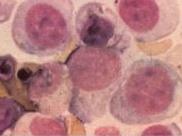

老年人巨幼細胞性貧血

• 老年人巨幼細胞性貧血

628健康網為您分享有關老年人巨幼細胞性貧血的癥狀,老年人巨幼細胞性貧血的治療方法,老年人巨幼細胞性貧血的預防知識...